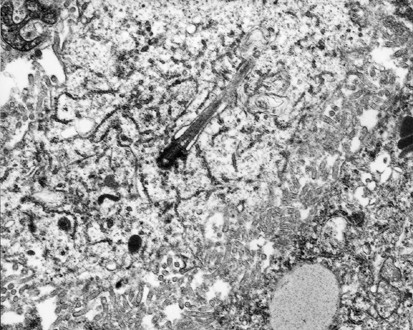

A mesothelioma cell showing an intracytoplasmic cilium (× 9000).